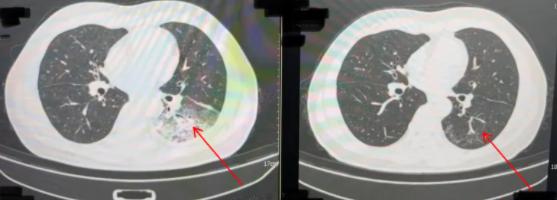

还有和陈先生同时住院的人。 32 岁姚女士(化姓)。根据她的介绍,家中的空调已经半年多没有清洗过了。,在住院之前,她在家里用了两天空调,一个星期后就出现了。咳嗽,咳痰,高热,寒颤,呕吐,腹泻,等待症状。当地诊所被诊断为“急性胃肠炎”,经初步治疗无效,病情恶化转移到当地医院呼吸和危重医学科继续治疗。

以前有姚女士 2 甲状腺恶性肿瘤型糖尿病(乳头状癌术后)、甲亢、特纳综合征等病史是甲状腺功能亢进,人群免疫力下降。经多次检查,姚女士最终被诊断为重症军团菌肺炎。用药调整后,患者病情迅速好转,体温逐渐恢复正常,各项指标逐渐恢复。